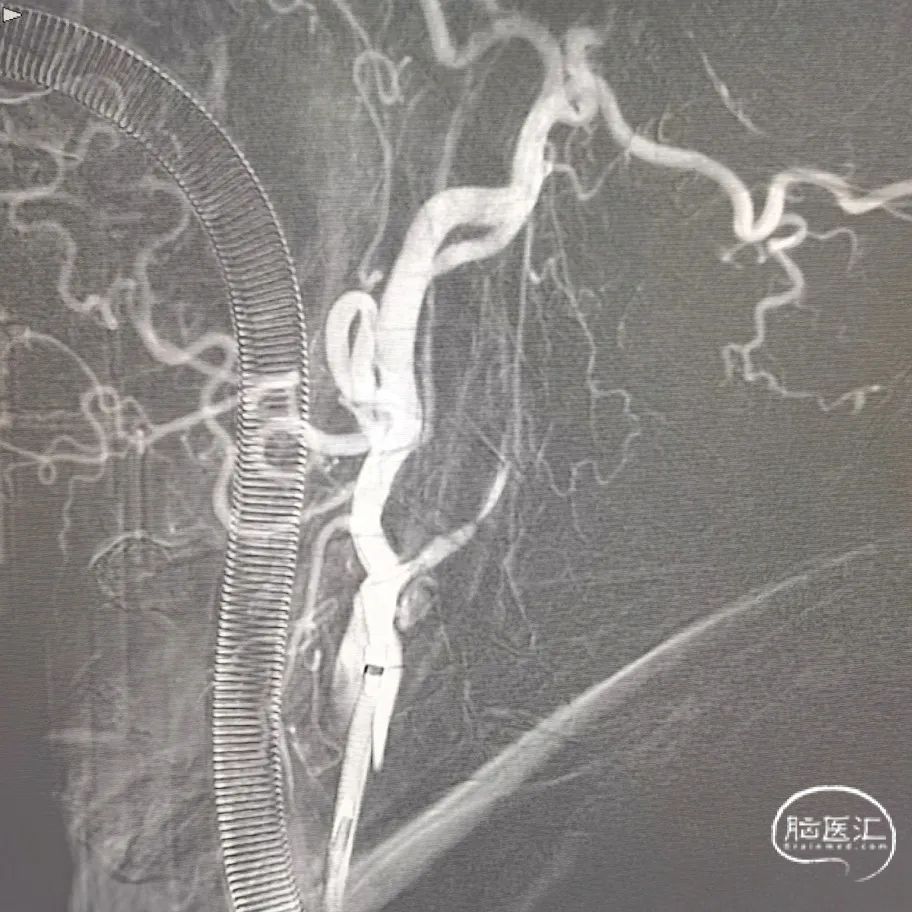

再次超选发现颈内动脉起始部重度狭窄伴夹层。

再次超选并将Syphonet®取栓支架释放后造影见血流通畅,回收取栓支架后血管再次闭塞,遂将4.5*28mm 支架置于大脑前动脉释放,支架释放后造影血流恢复满意。

通过中间导管将保护伞到位,退出中间导管,长鞘退至颈总动脉,4.5*30mm 球囊扩张颈内动脉狭窄段,球扩后满意,释放7*40mm 支架。